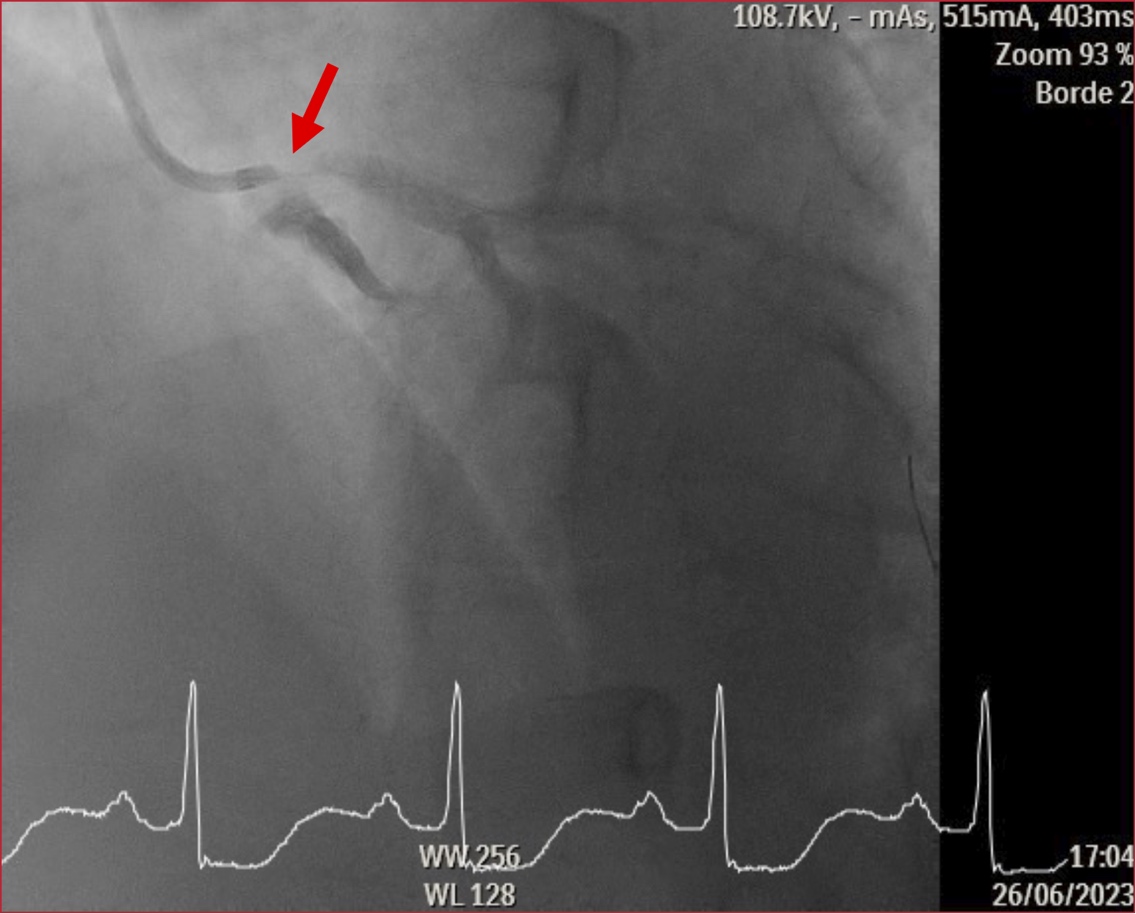

cambios dinámicos del segmento ST durante los episodios de angina, se realizó

un cateterismo emergente que mostró estenosis ostial severa del tronco

coronario izquierdo con luminograma liso, sugerente de compresión extrínseca

del vaso. No se consiguió cateterizar la arteria coronaria derecha, aunque, por

aortografía, se visualizó tardíamente el segmento medio-distal, aparentemente

de buen calibre y desarrollo, y con circulación heterocoronaria. El resto de

los vasos epicárdicos no tenía lesiones significativas (Figura 1).

Figura 1. Estenosis ostial severa del tronco coronario izquierdo, sugerente de compresión extrínseca.